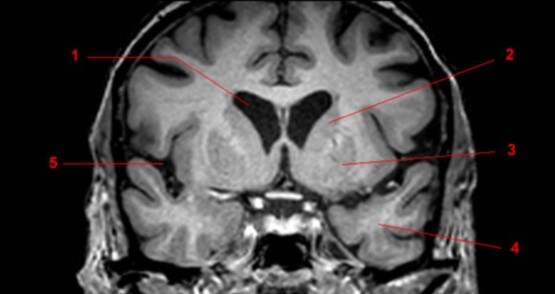

Label 1-5

1. Rt putamen

2. Rt globus pallidus

3. Rt Caudate nucleus

4. Lt Insula

5. Choroid plexus of left lateral ventricle